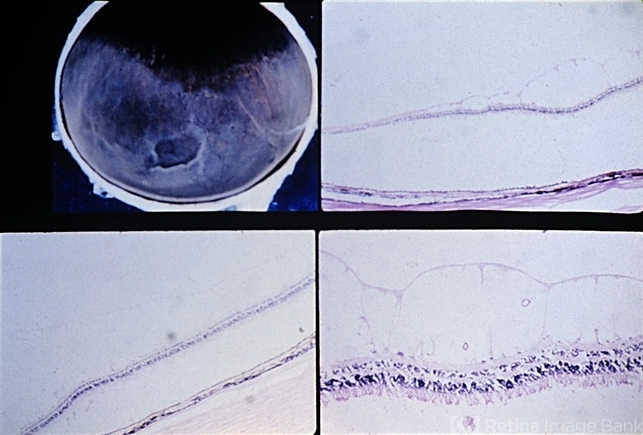

- retinoschisis, retinal pigment epithelium, hypertrophy, hyperplasia

- Reticular degenerative retinoschisis. In this case the process extends posteriorly from the equatorial area to the midperiphery. The gross view (upper left) also shows a band of dark pigmentation due to peripheral retinal pigment epithelial (RPE) hypertrophy, a few areas of paving-stone degeneration within the area of RPE hypertrophy, and peripheral retinal thinning with focal areas of RPE hyperplasia and migration into the retina.